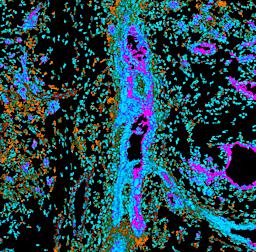

Pancreatic ductal adenocarcinoma is a lethal disease with limited treatment options and poor survival. We studied 83 spatial samples from 31 patients (11 treatment-naïve and 20 treated) using single-cell/nucleus RNA sequencing, bulk-proteogenomics, spatial transcriptomics and cellular imaging. Subpopulations of tumor cells exhibited signatures of proliferation, KRAS signaling, cell stress and epithelial-to-mesenchymal transition. Mapping mutations and copy number events distinguished tumor populations from normal and transitional cells, including acinar-to-ductal metaplasia and pancreatic intraepithelial neoplasia. Pathology-assisted deconvolution of spatial transcriptomic data identified tumor and transitional subpopulations with distinct histological features. We showed coordinated expression of TIGIT in exhausted and regulatory T cells and Nectin in tumor cells. Chemo-resistant samples contain a threefold enrichment of inflammatory cancer-associated fibroblasts that upregulate metallothioneins. Our study reveals a deeper understanding of the intricate substructure of pancreatic ductal adenocarcinoma tumors that could help improve therapy for patients with this disease.